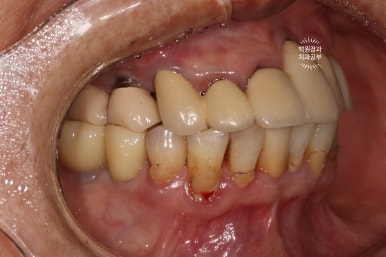

저희 치과에 다니시던 70대 여자 환자분입니다.

잘 보시면, 임플란트가 총 위턱에 9개, 아래턱에 2개 되어있는데 대부분이 아주 유명한 외국 임플란트 제품들입니다. 특히나 위턱 어금니는 스트라우만 standard 제품으로, 제가 가장 신뢰하는 제품 중 하나입니다.

무려 20년이 넘으셨다고 했는데... 임플란트 주위염 하나 없이 너무너무 잘 사용하고 계시더라구요.

처음 오셨을 때 정면 사진입니다.

잘 보시면, 아까 보였던 치과용 파노라마 사진대로 뿌리만 남은 두 개의 치아를 찾아보실 수 있으실거에요. ㅎㅎ

제가 서두에서 어금니에 스트라우만 임플란트가 많다고 말씀드렸는데, (나머지도 branemark 제품으로 보이며, 명품으로 주름잡던 스웨덴 임플란트 입니다.) 이 미친 퍼포먼스의 스위스 임플란트는 20년이 지난 지금도 짱짱한 성능을 자랑하고 있답니다.

사실 구강위생관리가 그렇게 완벽하신편이 아니신데도.. 이런 임상결과를 보이고 있는 것이 늘 경이롭습니다.